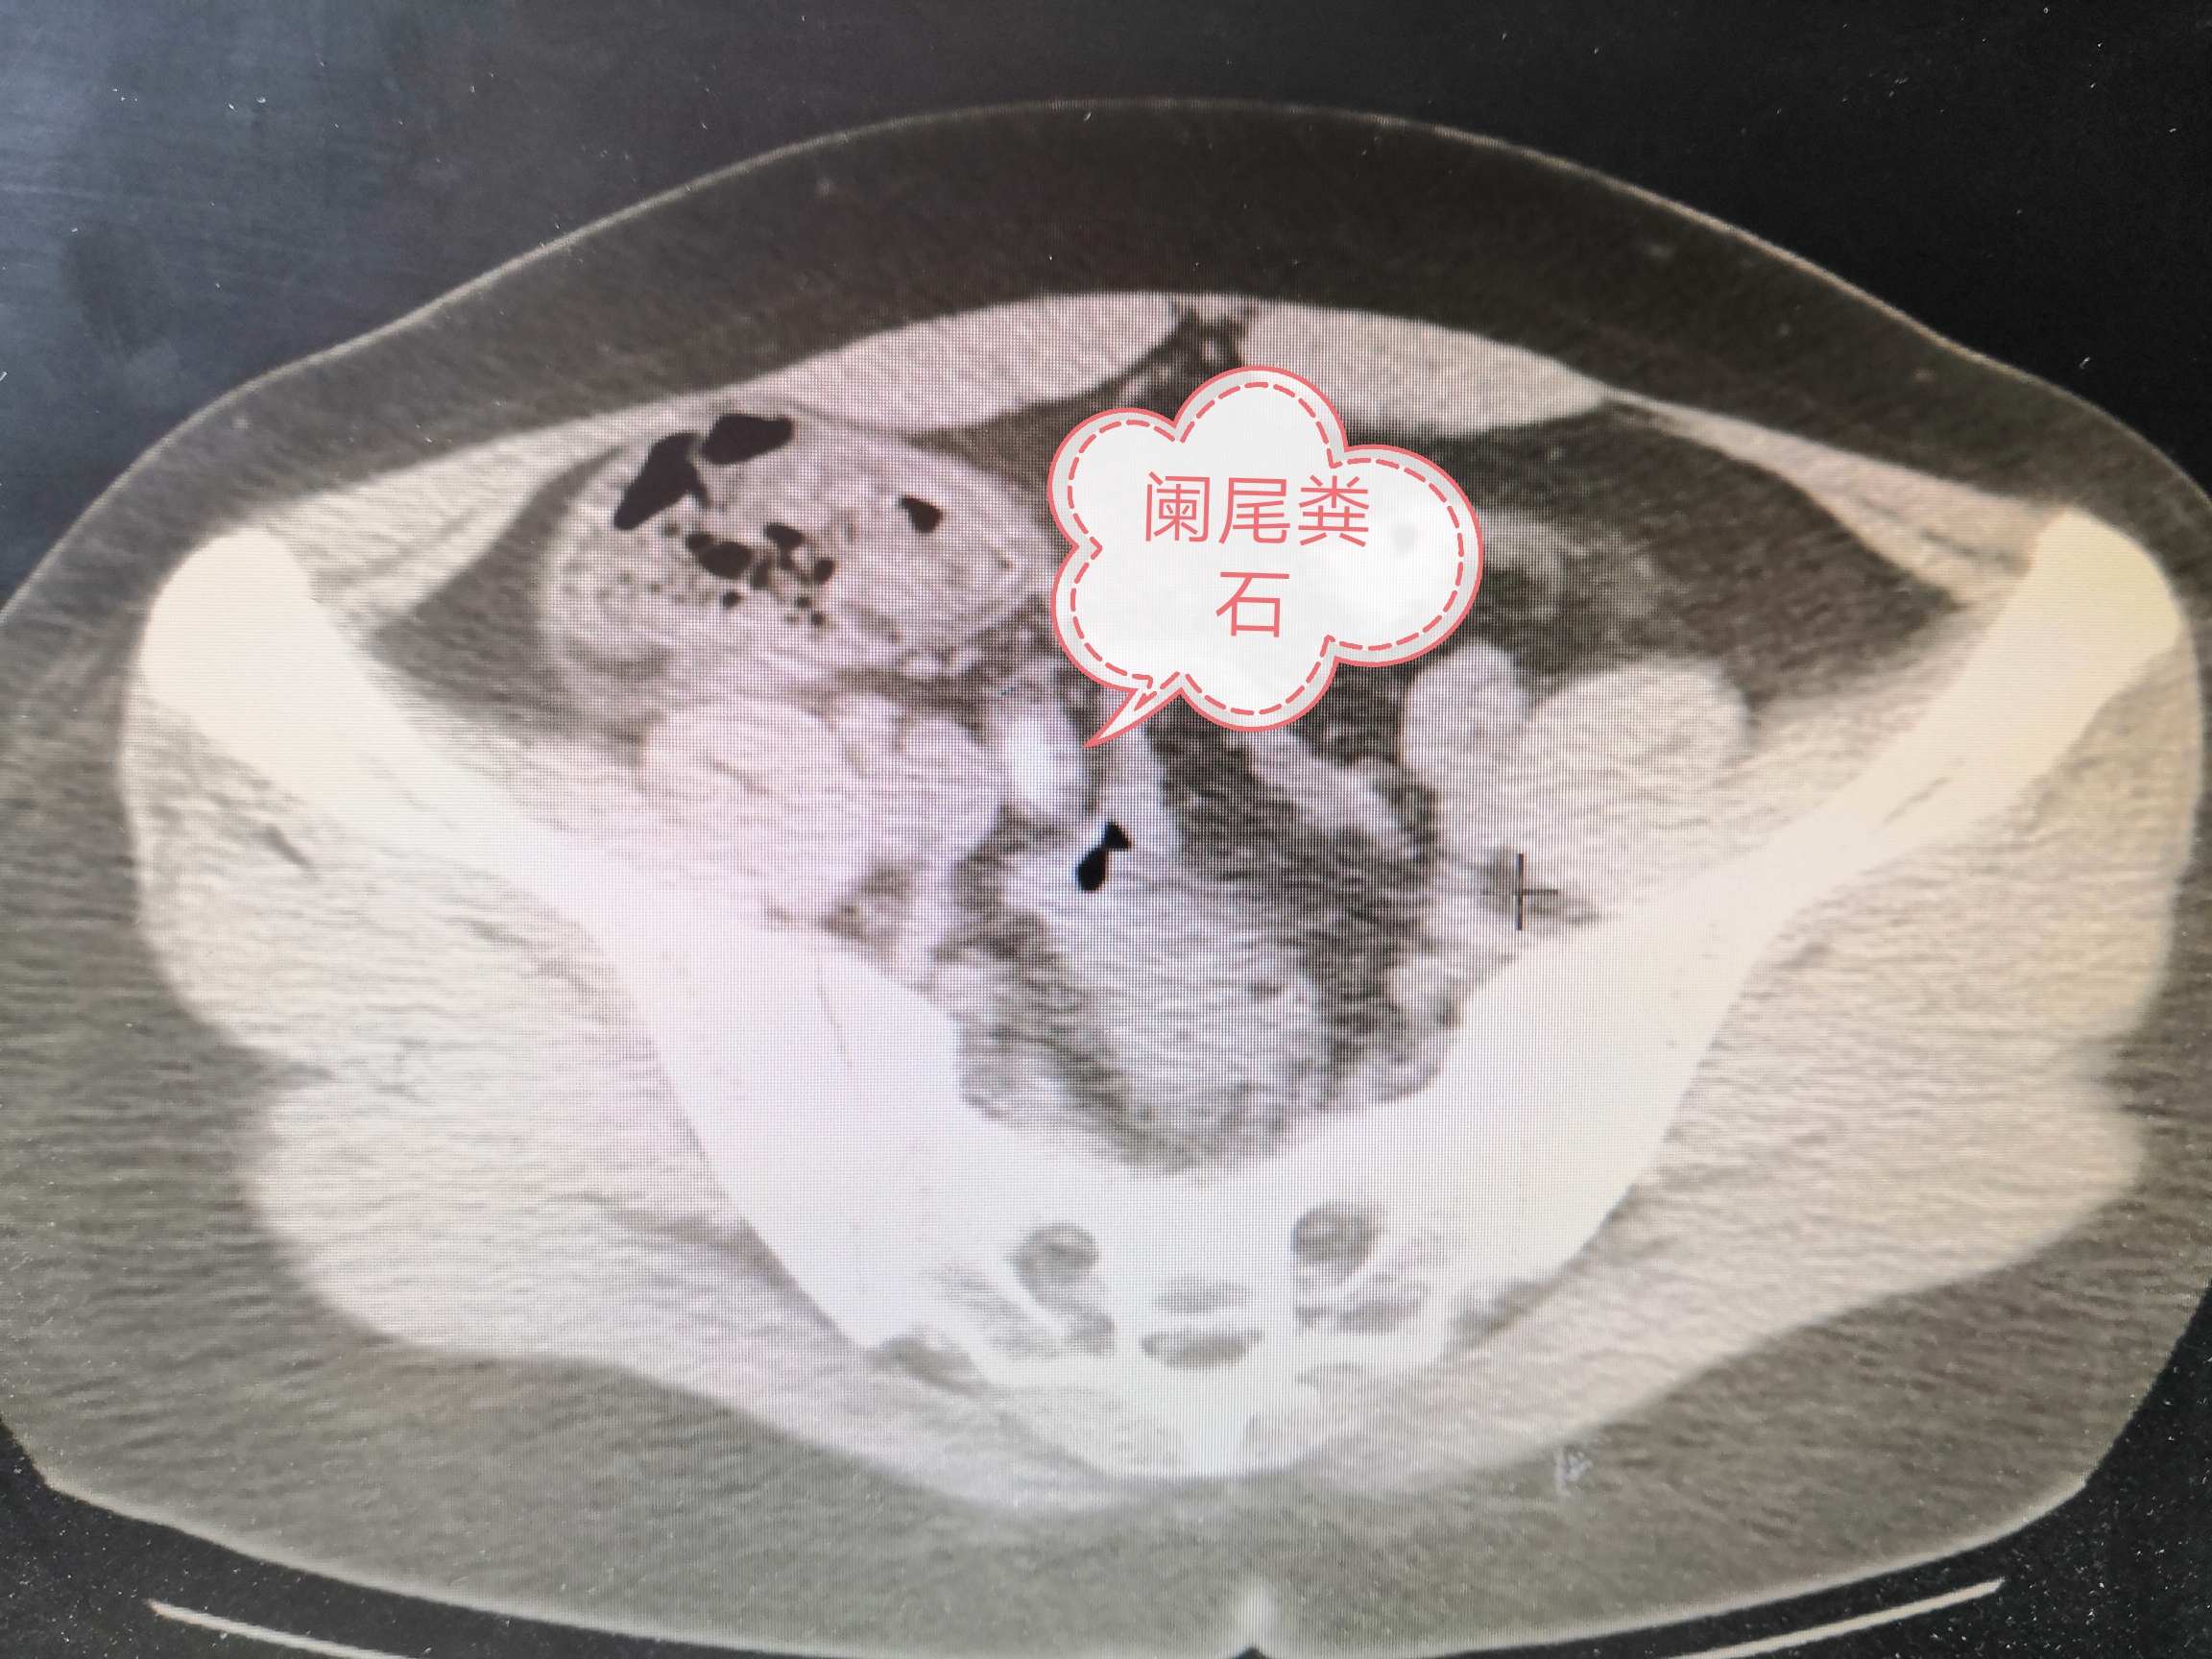

不一会儿查血结果出来了血常规提示炎症指标比较高,淀粉酶也有轻微升高,做了阑尾区B超提示阑尾增粗,并且阑尾内有粪石(可以简单理解为长期积存的大便形成的石头)。

小妹妹和家属要求做腹部CT,很快腹部CT结果出来了,仍考虑急性阑尾炎,并且阑尾内有粪石嵌顿(就是卡在阑尾里了)。

手术过程中,发现阑尾又粗又长,根部有一个粪石,阑尾已经穿孔,腹腔内有较多脓液,切除阑尾、吸净脓液后给予放置一根引流管(一般情况下不放置引流管)。